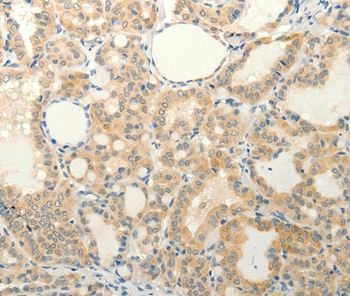

Immunohistochemical analysis of paraffin-embedded Human thyroid cancer tissue using #37294 at dilution 1/20.

Immunohistochemical analysis of paraffin-embedded Human liver cancer tissue using #37294 at dilution 1/20.